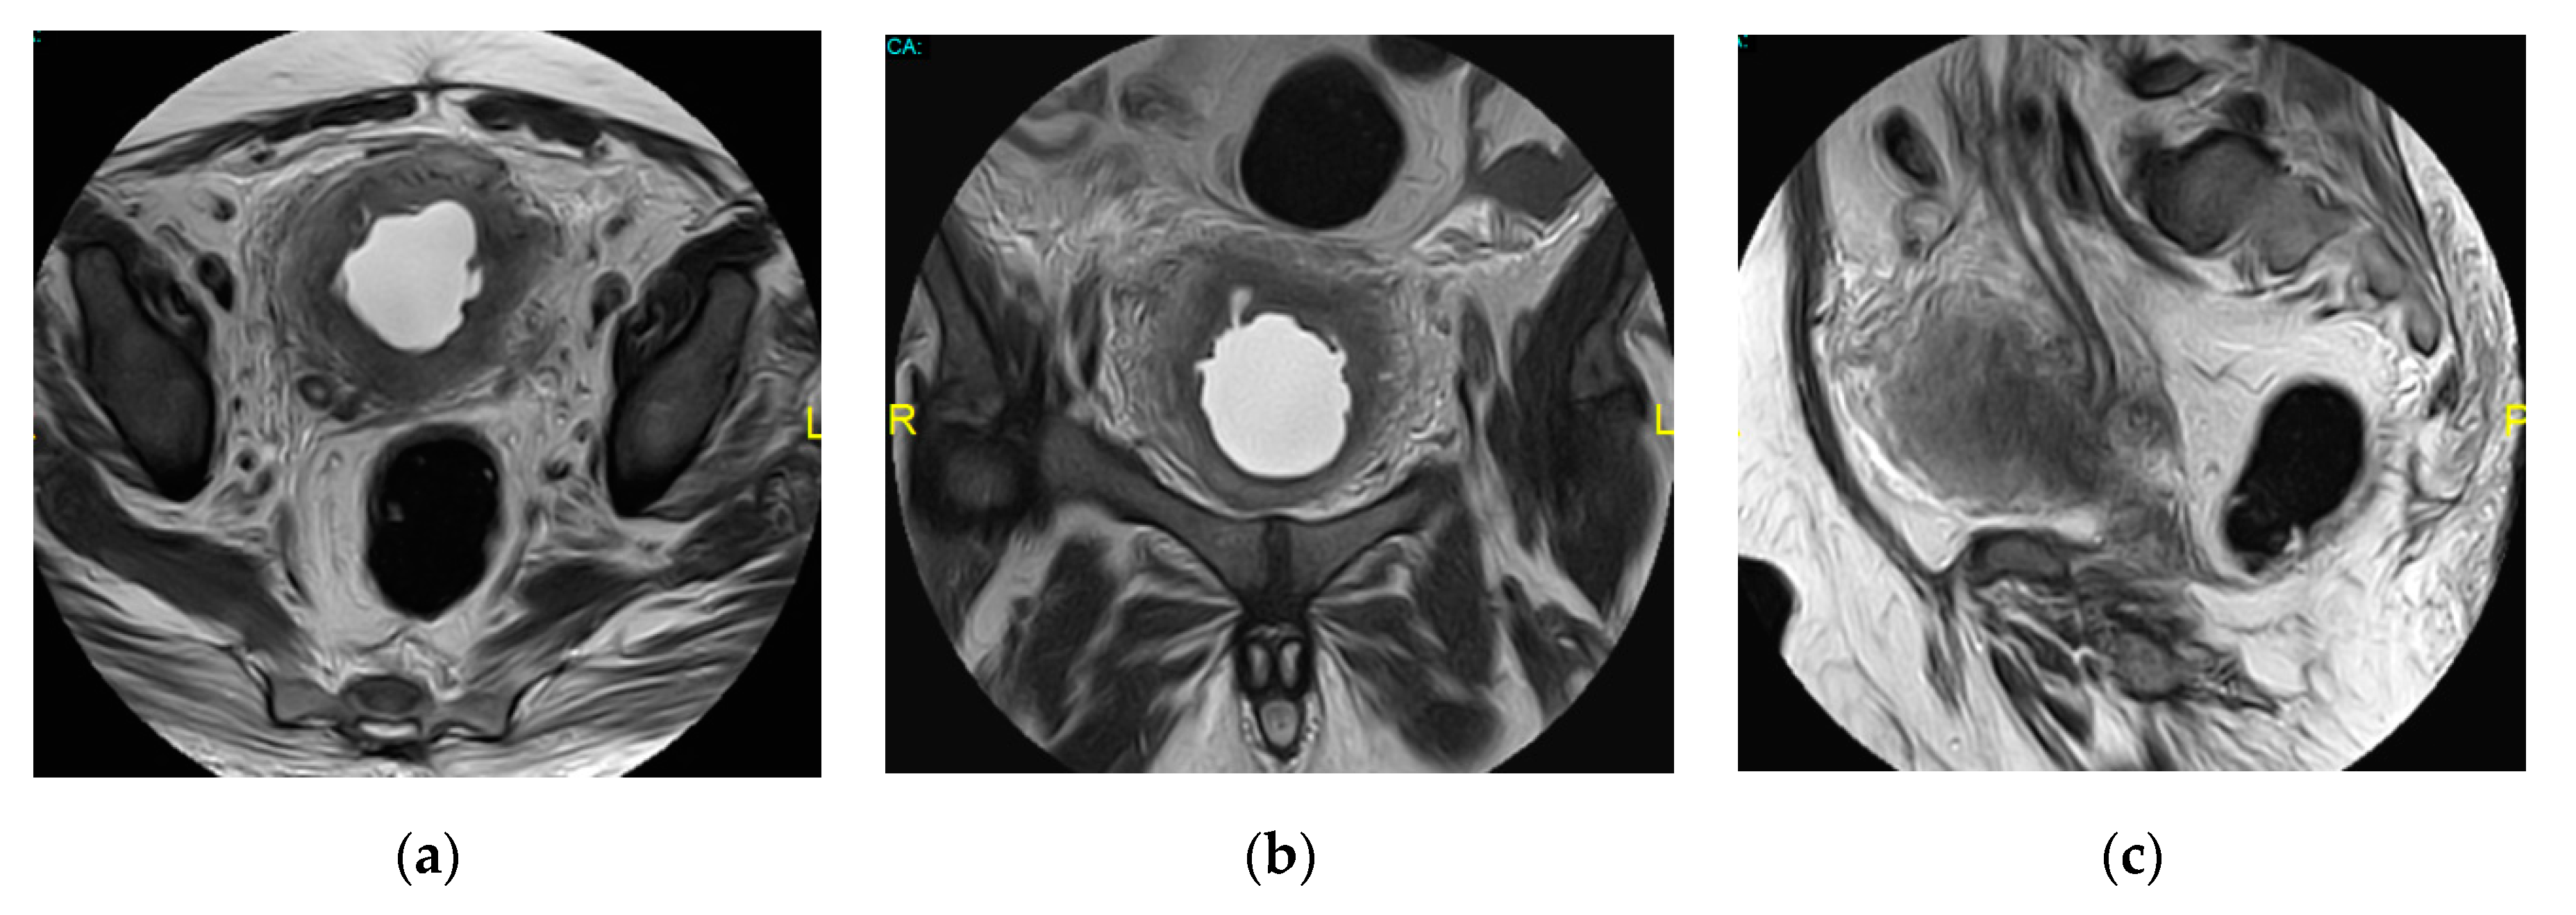

2.15. Acute Bacterial Prostatitis and Prostatic Abscess

- Ren, J.; Huang, X.; Wang, H.; Liu, H.; Ren, F.; Zhang, Z.; Yang, Y.; Yin, H.; Huan, Y. Prostatic abscess and seminal vesicle abscess: MRI findings and quantitative analysis of apparent diffusion coefficient values. Radiol. Infect. Dis. 2015, 2, 27–32. [Google Scholar] [CrossRef]

| Prostatic abscess | Non enhancing fluid collection with peripheral or septal enhancement and non-enhancing central fluid. Possible extraprostatic extension |